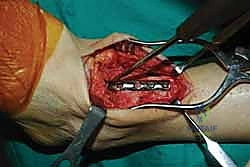

- رؤية ممتازة للمفصل: يوفر المدخل الأمامي رؤية بانورامية واسعة ومباشرة لكامل السطح المفصلي للظنبوب وعظم الكاحل، مما يسمح بإزالة الغضاريف التالفة بدقة متناهية.

- تصحيح التشوهات بدقة: يسمح هذا المدخل بتعديل انحرافات الكاحل (سواء كان يميل للداخل Varus أو للخارج Valgus) وإعادته إلى المحور الميكانيكي الطبيعي للساق.

- تجنب الأعصاب والأوعية الدموية الرئيسية: رغم وجود الحزمة الوعائية العصبية الأمامية (الشريان الظنبوبي الأمامي والعصب الشظوي العميق)، إلا أن الجراح المتمرس مثل الدكتور هطيف يقوم بعزلها وحمايتها بدقة تامة.

خطوات جراحة تثبيت مفصل الكاحل الأمامي بالتفصيل (Step-by-Step Surgical Procedure)

تُجرى العملية تحت التخدير العام أو النصفي (الشوكي)، وتستغرق عادةً بين ساعتين إلى ثلاث ساعات، وتتطلب دقة ومهارة فائقتين. إليكم الخطوات الجراحية كما ينفذها الأستاذ الدكتور محمد هطيف:

1. الوضعية والشق الجراحي (Positioning and Incision)

يستلقي المريض على ظهره (Supine position). يتم استخدام عاصبة (Tourniquet) حول الفخذ لتقليل النزيف وتوفير رؤية واضحة. يقوم الدكتور هطيف بإجراء شق طولي أمامي فوق مفصل الكاحل، عادة بين وتر العضلة الظنبوبية الأمامية (Tibialis Anterior) ووتر العضلة الباسطة الطويلة لإصبع القدم